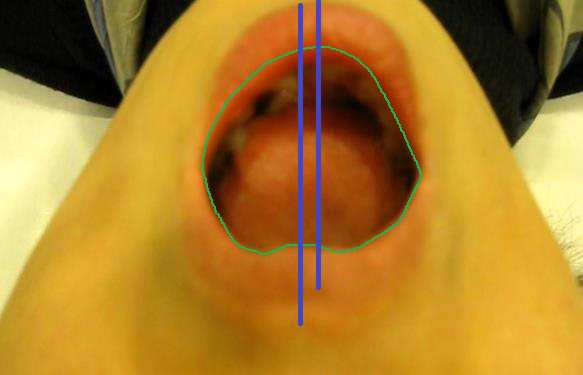

아래턱을 벌려 보면서 아랫니의 중간부분이 이 가상의 중간선에을 따라 잘 벌어지는지 관찰해 봅니다

반듯하게 벌어지는 분들은 거의 없습니다.